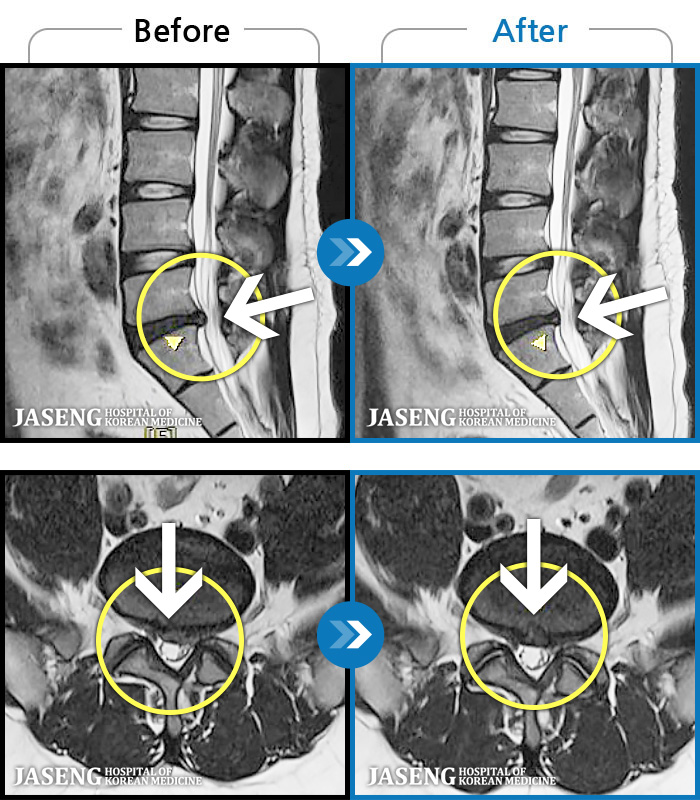

MRI 치료사례

양측 허리 통증과 좌측 허벅지까지 동반되는 저림증상 있고, 앉거나 걸을 때 통증 심화되어 내원하셨습니다.